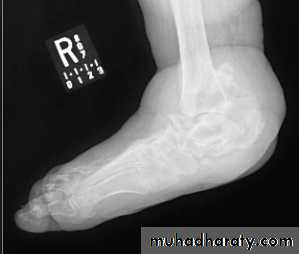

GOUT

• Heterogeneous group of entities characterized by recurrent attacks of arthritis secondary to deposition of sodium urate crystals in and around joints.• *90% of patients are male

• *Causes due to either Uric acid overproduction, 10% or underexcretion, 90%.

• Radiographic features

• *Lower extremity > upper extremity; small joints > large joints

• * First MTP is most common site

• * Marginal, peri articular erosions: overhanging edge

• * Erosions may have sclerotic borders

• * Joint space is preserved

• * Soft tissue and bursa deposition

• Tophi: juxtaarticular, helix of ear

• Bursitis: olecranon, prepatellar

• * Erosions and tophi only seen in longstanding disease

• * Tophi calcification, 50%

• *Chondrocalcinosis

NEUROPATHIC ARTHRITIS (CHARCOT'S JOINT)

• Primary loss of sensation in a joint leads to arthropathy. Distribution helps determine etiology.• Causes

• Diabetes neuropathy: usually foot